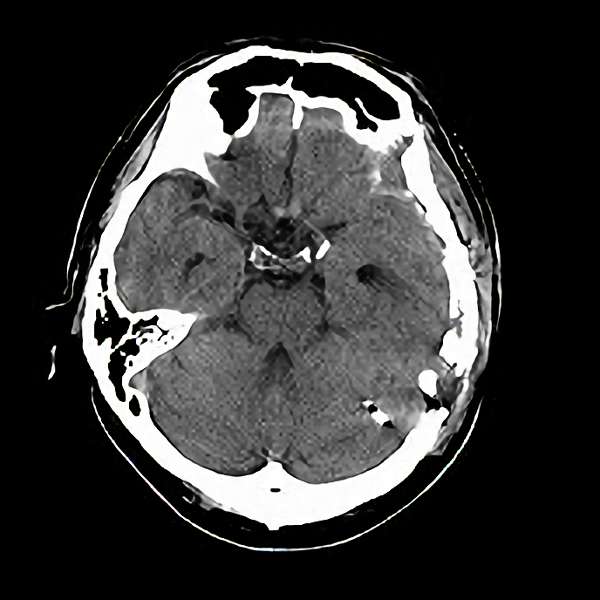

脳血管撮影

手術前

手術後

手術中

モニタリング

手術写真

手術の結果